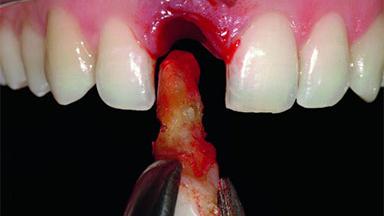

A 32-year-old female Caucasian patient with a compromised maxillary right central incisor was referred to us by a general dentist. Her chief complaints were discomfort and mobility of tooth 11 with unsatisfactory esthetics due to discoloration. The patient reported a previous trauma, some years earlier, as the origin of pathology on the afflicted tooth. Anamnesis was negative for any other dental or periodontal pathology in the remaining dentition. The patient did not take any medication and reported to be a light smoker (5–10 cigs/day). She had high esthetic expectations of her treatment. The extraoral examination revealed a high smile line with full exposure of her maxillary teeth and surrounding soft tissue in the area between the second premolars.

| Bone Volume | Deficient horizontally, requiring prior grafting |